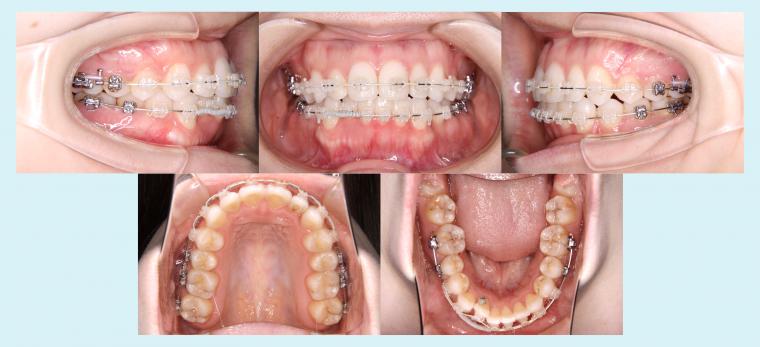

#50 非抜歯で叢生を改善した症例